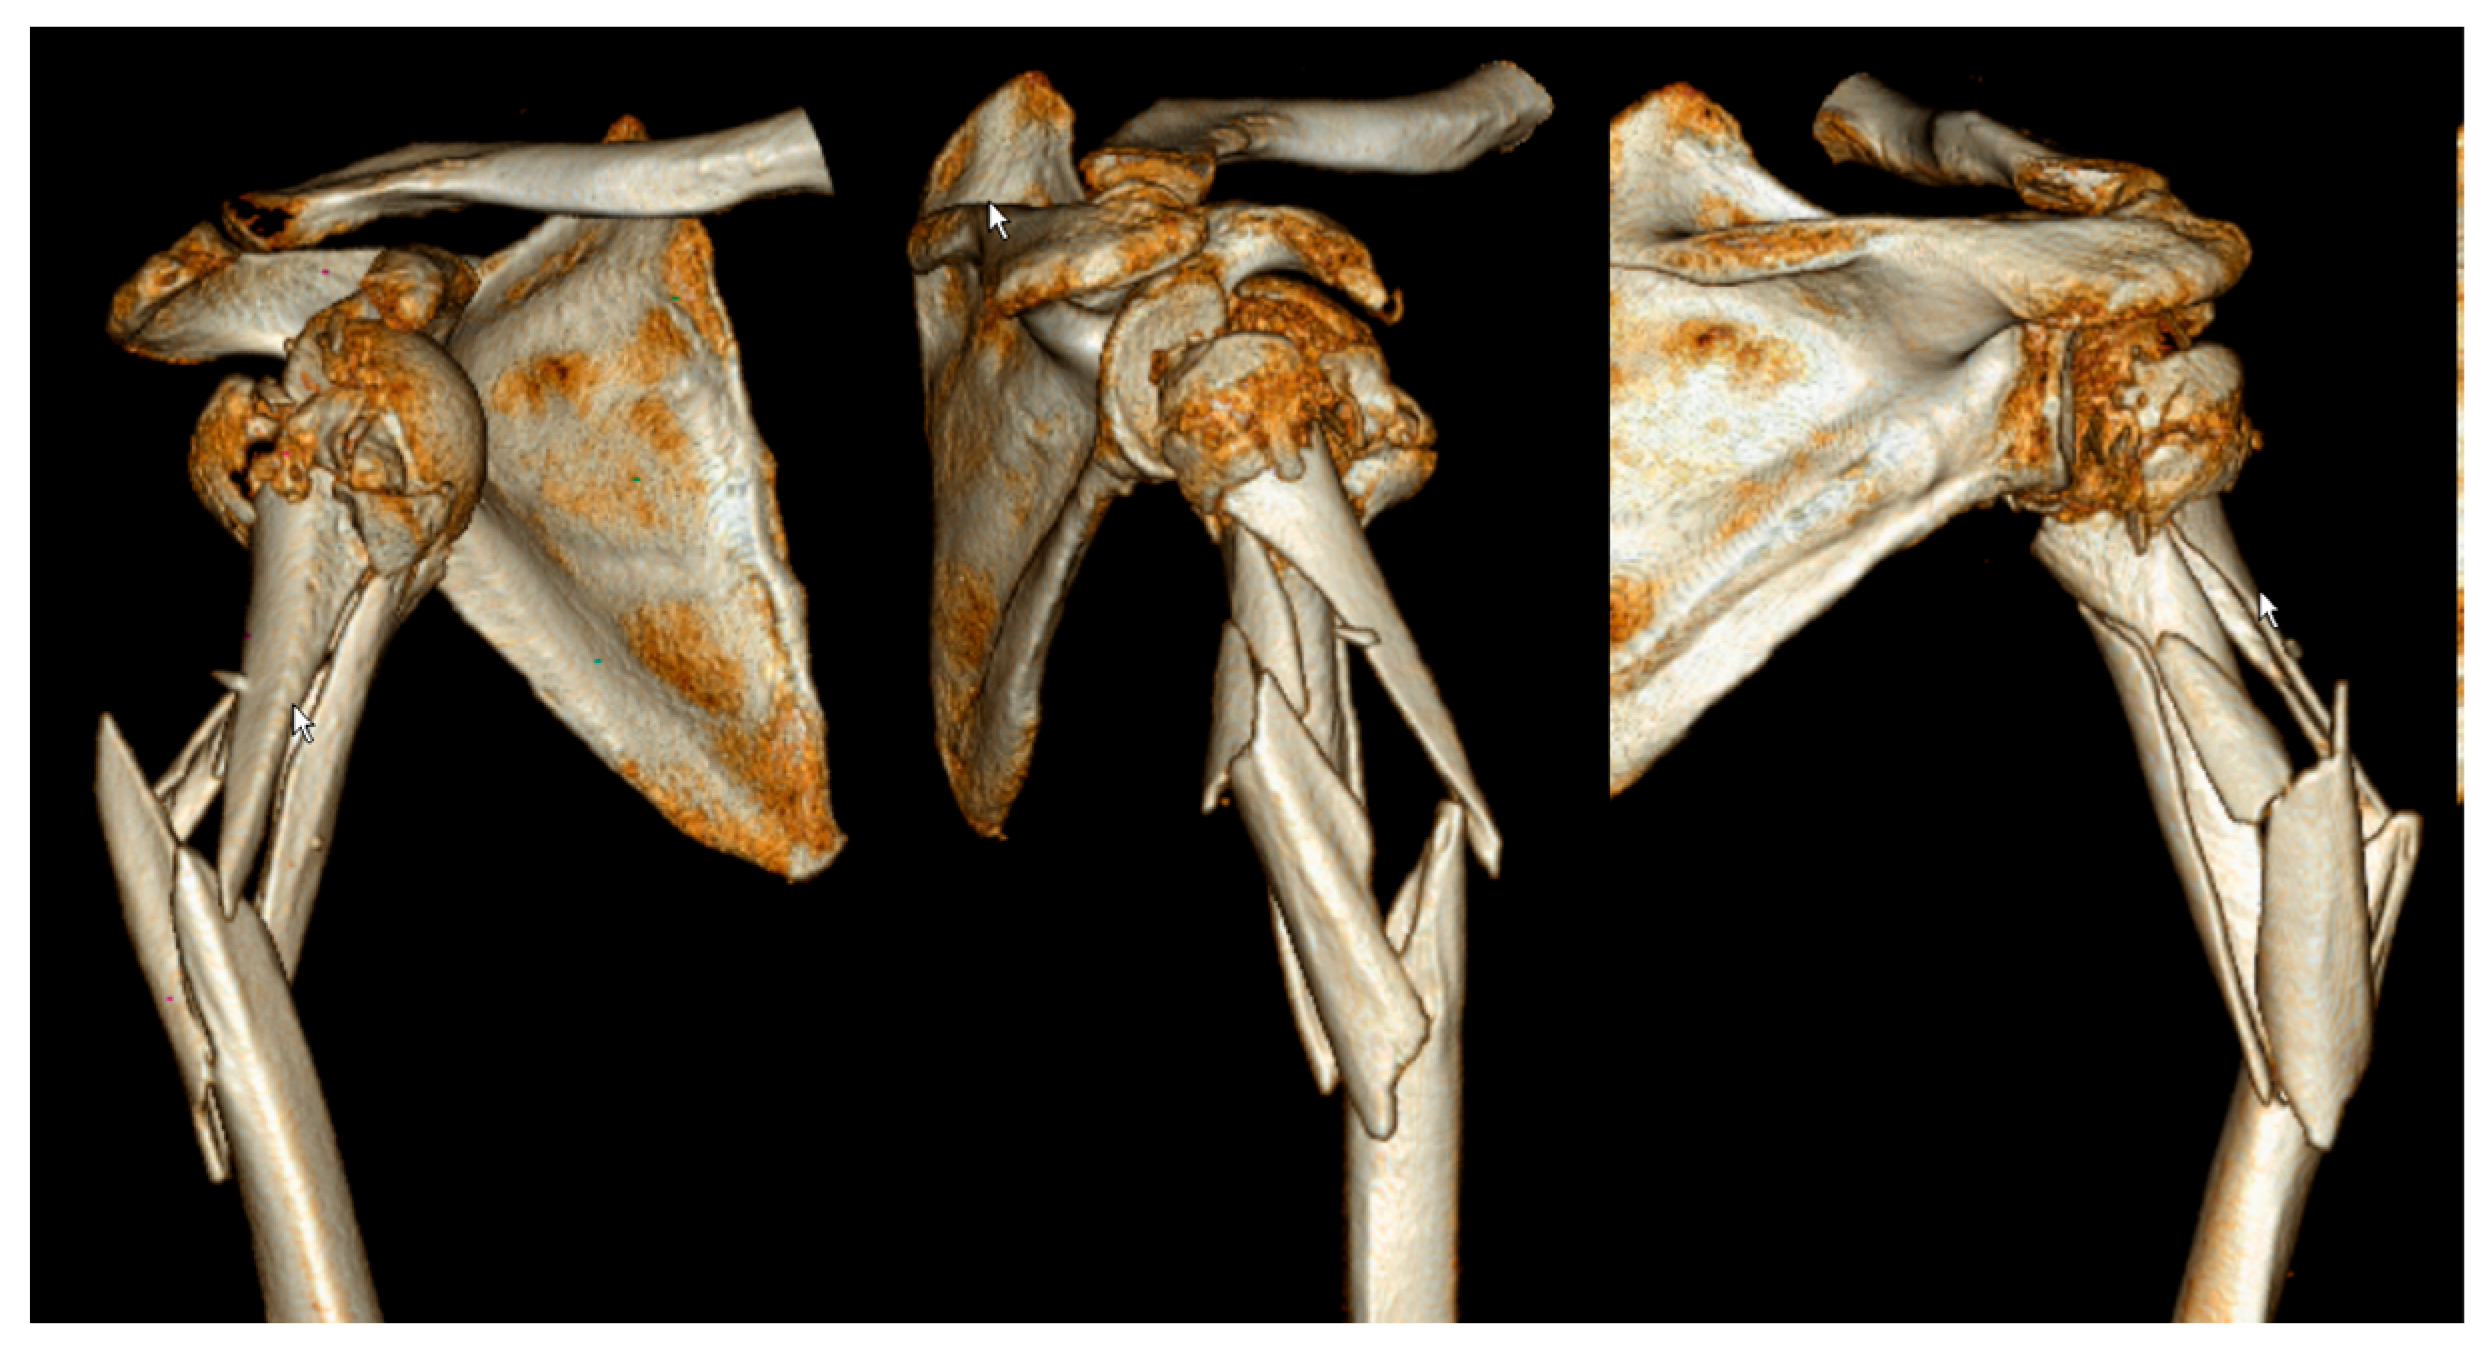

| Case | Age, years | Sex | Neer | AO/OTA Proximal | AO/OTA Metaphyseal | Stedtfeld | Garnavos/ Lasanianos | Implant/ Metaphyseal Fixation | FU, Months/ CMS-K | Revision |

|---|---|---|---|---|---|---|---|---|---|---|

| 1 | 65 | M | IV | 11-B1 | 12-C2 | D4 | Combined | Retrograde nail | 48/83 | - |

| 2 | 74 | F | III | 11-A3 | 12-C3 | A2 | Extended | T-nail | 97/51 | Metaphyseal lack of fixation, material removal |

| 3 | 68 | F | IV | 11-B1 | 12-C1 | D2 | Extended | T-nail | 32/71 | Metaphyseal lack of fixation, change to plate |

| 4 | 43 | M | IV | 11-B1 | 12-C3 | D3 | Extended | T-nail/cerclage | 92/77 | - |

| 5 | 74 | F | V | 11-B2 | 12-C1 | B1-3 | Extended | T-nail/screw | 52/64 | - |

| 6 | 65 | M | III | 11-A2 | 12-A1 | A2 | Extended | T-nail/screw | 60/62 | - |

| 7 | 75 | F | III | 11-A2 | 12-C1 | C3 | Extended | T-nail | 91/64 | - |

| 8 | 72 | F | VI | 11-C3 | 12-C3 | D3 | Extended | T-nail/screw | 55/68 | Metaphyseal lack of fixation, inverse prothesis |

| 9 | 55 | F | III | 11-A2 | 12-C1 | B2-1 | Extended | T-nail | 70/99 | - |

| 10 | 67 | F | III | 11-A2 | 12-C1 | C2 | Extended | Locking plate/ cerclage, lag screw | 63/99 | - |

| 11 | 37 | F | IV | 11-B1 | 12-C1 | D3 | Extended | T-nail/screw | 34/86 | - |

| 12 | 50 | F | III | 11-A2 | 12-C1 | C4 | Combined | T-nail/cerclage | 49/97 | - |

| 13 | 76 | F | V | 11-C2 | 12-C2 | D4 | Combined | Locking plate/ lag screw | 58/65 | - |

| 14 | 71 | M | IV | 11-B1 | 12-C1 | D4 | Extended | T-nail/screw | 15/38 | Loss of reduction, proximal nail displacement, material removal |

| 15 | 70 | F | IV | 11-B1 | 12-C2 | D4 | Combined | T-nail/cerclage | 15/70 | - |

| 16 | 23 | M | IV | 11-B2 | 12-C2 | D4 | Combined | Locking plate/ plate | 35/99 | - |

| 17 | 46 | F | V | 11-C2 | 12-C3 | B1-3 | Extended | Locking plate/ lag screw | 57/100 | - |

| 18 | 76 | F | III | 11-A2 | 12-C1 | C2 | Extended | T-nail | 12/72 | - |

| 19 | 53 | F | III | 11-A3 | 12-C3 | C3 | Extended | T-nail/screw | 12/48 | Metaphyseal lack of fixation, change to plate |

| 20 | 53 | F | IV | 11-B1 | 12-A1 | B2-3 | Extended | T-nail | 12/74 | - |

| 21 | 51 | F | IV | 11-B1 | 12-C1 | D2 | Extended | Locking plate/ lag screw | 37/89 | - |

| 22 | 49 | M | V | 11-C2 | 12-C3 | D2 | Combined | Locking plate/ plate | 61/50 | - |

| 23 | 48 | F | V | 11-C2 | 12-C3 | B1-3 | Extended | Locking plate | 45/84 | - |

| 24 | 68 | M | IV | 11-B1 | 12-C1 | B1-2 | Extended | Locking plate/ lag screw | 12/45 | Metaphyseal lack of fixation, pseudarthrosis |

| 25 | 74 | F | III | 11-C1 | 12-C3 | C3 | Extended | Locking plate/ cerclage | 13/62 | - |